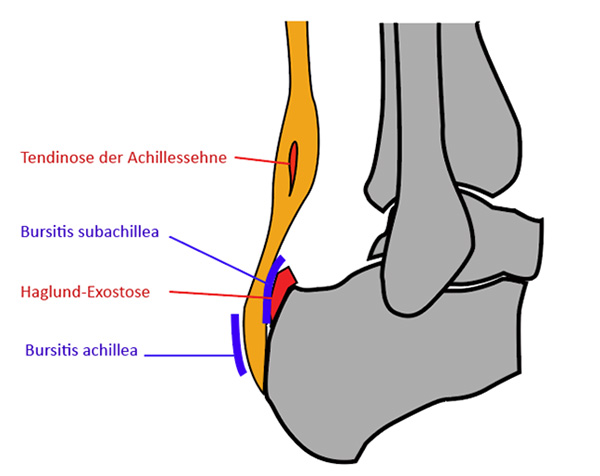

Abzugrenzen ist hiervon die Insertionstendopathie, die sich durch einen Schmerz am Sehnen-Knochen-Übergang auszeichnet. Etwas kranial davon am posterioren und superioren Kalkaneus finden sich die Beschwerden bei einer Haglundexostose. In vielen Fällen finden sich klinische Mischbilder aus Haglundexostose mit Bursitis subachillea und einer Ansatztendinose der Achillessehne 7.

Abbildung 20: Ansatznahe Pathologien der Achillessehne (J. Dohle).